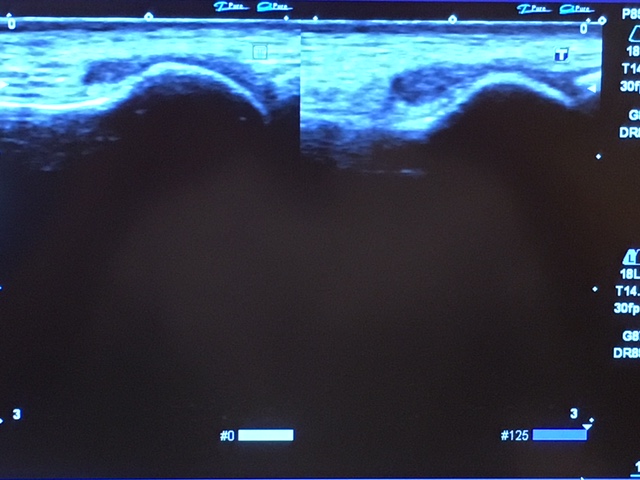

次にエコーです。

基本的には、

圧痛部位を、左右と比較します!

左が患側 右が健側です。

どうですか?

骨の大きさの違い一目でわかります。

左のほうが大きくなってます。